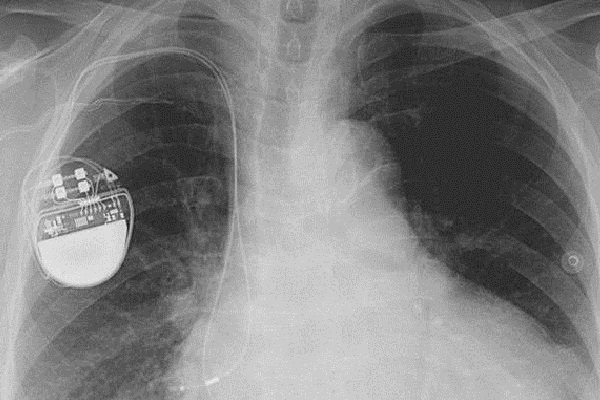

کارشناسان امنیتی هشدار می دهند که هکرها می توانند با نفوذ به دستگاه های تنظیم ضربان قلب که در داخل بدن انسان کار گذاشته می شود، زندگی این بیماران را به خطر بیندازند.

به گزارش سیتنا به نقل از گیزمودو، بسیاری از تجهیزات پزشکی مبتنی بر فناوری اطلاعات مانند پمپ های تزریق انسولین و دستگاه های تنظیم کننده ضربان قلب از آسیب پذیری هایی برخوردار هستند که دستکاری آنها برای هکرها را ممکن می کند.

محققان شرکت امنیتی وایت اسکوپ می گویند دستگاه های تنظیم ضربان قلب ۴ شرکت مشهور سازنده این نوع تجهیزات و همین طور سیستم های مورد استفاده برای کنترل و بررسی عملکرد دستگاه های یاد شده در مجموع دارای ۸۰۰۰ آسیب پذیری مختلف هستند و این تعداد بی سابقه از اشکالات بسیار نگران کننده است.

کارشناسان وایت اسکوپ می گویند سیستم های نرم افزاری تولیدات هر چهار شرکت قدیمی و به روز نشده بوده و اطلاعات خصوصی مربوط به هر بیمار به طور رمزگذاری نشده بر روی آنها ذخیره می شود. لذا در زمان اتصال آنها به سیستم های نظارتی بدون نیاز به ورود کلمه عبور می توان به این اطلاعات دسترسی پیدا کرد.

این اولین بار نیست که هشدارهایی در مورد امنیت پایین تجهیزات حساس پزشکی منتشر می شود. در سال ۲۰۱۳ هم هکری به نام بارنابی جک از فاصله ۱۵ متری توانسته بود شوکی مرگبار به یک دستگاه کنترل ضربان قلب وارد کند، اما شرکت های سازنده این نوع تجهیزات هشدارهای یاد شده را جدی نمی گیرند.